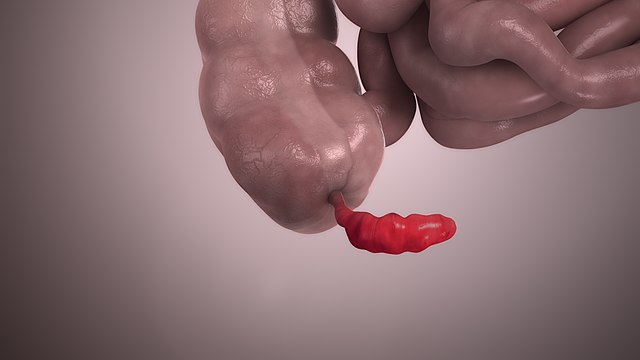

Λαπαροσκοπική Σκωληκοειδεκτομή